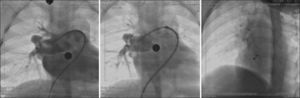

Two patients had associated heart defects, treated percutaneously in the same procedure. One had moderate pulmonary valve stenosis and was submitted to balloon pulmonary valvuloplasty prior to ASD occlusion. The other patient had pulmonary arteriovenous fistula presented in right lung base that resulted in significant cyanosis, which was successfully occluded with the Amplatzer® Duct Occluder II (Figure 7).

– To the left, coronary angiography demonstrating the presence of large pulmonary arteriovenous fistula originating from the middle lobar branch of the right pulmonary artery. In the center, control coronary angiography showing good prosthesis positioning, with fistula occlusion. To the right, chest fluoroscopy in the left oblique projection with cranial angulation showing the spatial association between the implanted prosthesis in the fistula and in the atrial septal defect (Amplatzer® ADO II and Amplatzer® ASD).